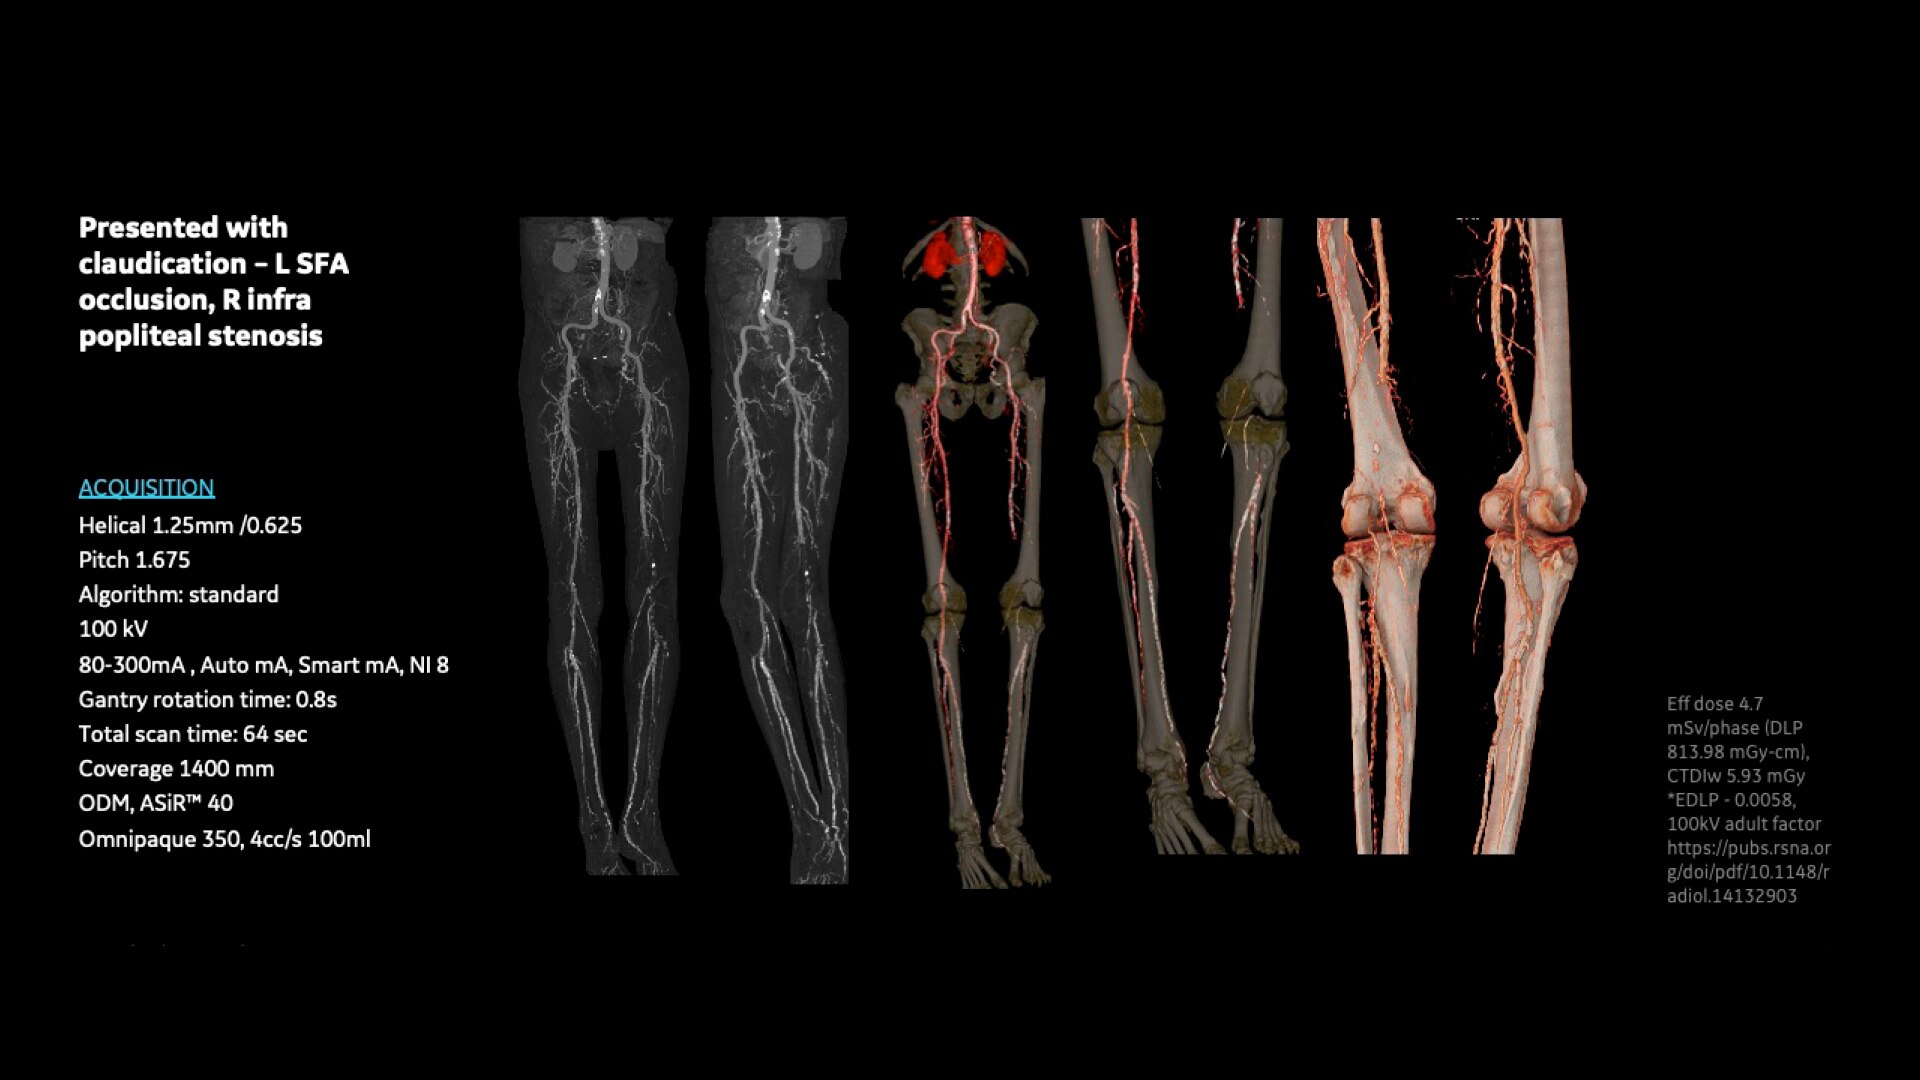

Organ Dose Modulation (ODM) – Achieves a reduced radiation dose of up to 40% via X-ray tube current modulation for superficial organs and tissues, such as breasts, and maintains diagnostic quality without decreasing productivity.

Vascular Imaging and Processing – Enhances analysis of vascular features by automatically determining vessel centerline and tracking multiple vessels.